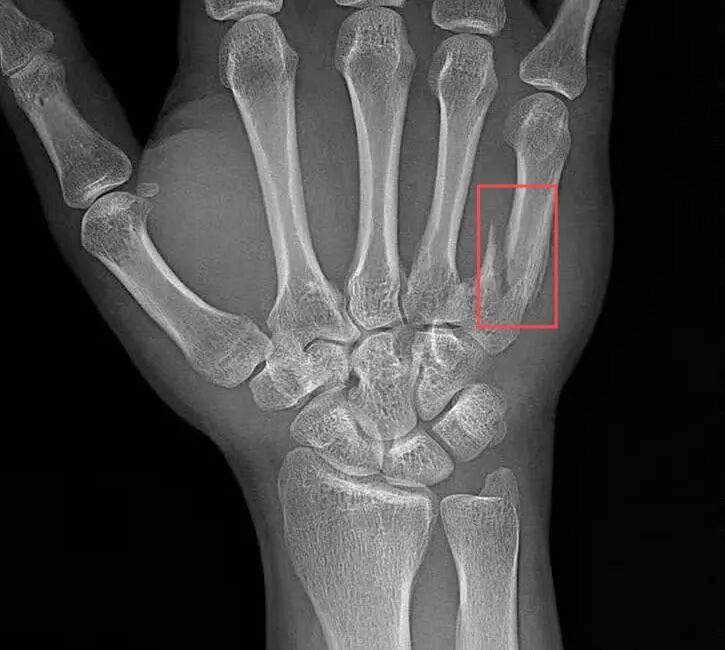

2025年3月8日,夏先生因意外受伤前往玉溪市中山医院骨科就诊,经详细检查会诊,诊断夏先生为右手第五掌骨骨折。骨科团队迅速为其制定个性化治疗方案,并于3月13日成功实施“掌骨骨折切开复位钢板内固定术”,手术由曾润华与韩振宏两位医生主刀。凭借丰富的临床经验与精湛的微创技术,两位医生顺利完成手术。术后,夏先生恢复良好,疼痛明显减轻。同时,医护人员每日密切监测夏先生病情、耐心指导其进行康复训练,夏先生手部功能逐步恢复,于3月17日顺利出院。

术前患者右手第五掌骨骨折